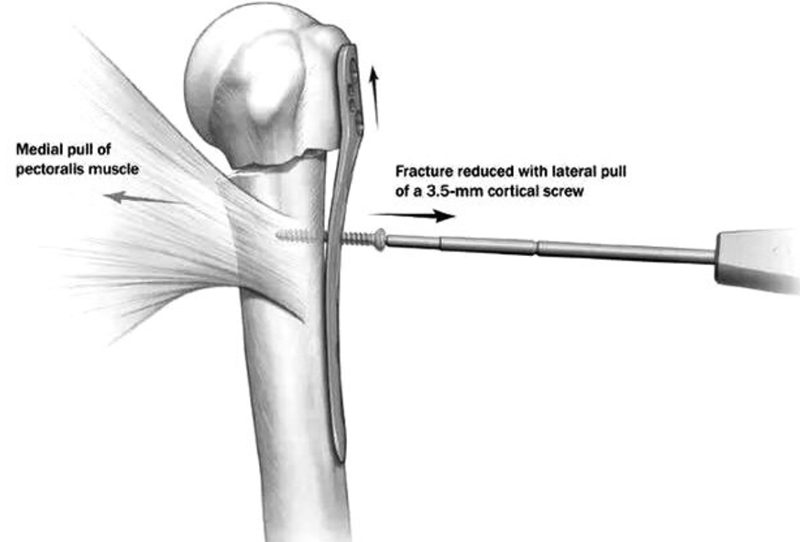

(5)由于胸大肌的牵拉,肱骨干通常都向内移位。

图14 可以先将钢板固定在肱骨头外侧面,而此时骨干可能仍然存在向内移位,在骨折线远端的第一个螺钉孔置入一枚3.5mm皮质骨螺钉将肱骨干向外提拉复位

图15 通过提拉,达到解剖复位